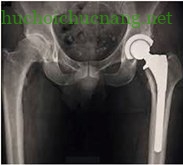

Thay khớp háng toàn phần (thay các mặt khớp của xương đùi và của ổ chảo): Áp dụng cho các trường hợp đau do viêm hay thoái hoá khớp háng, hoặc gãy cổ xương đùi ở người già.

Thay khớp háng toàn phần Thay khớp háng bán phần

Thay khớp háng bán phần: Thường được chỉ định cho những người bị gãy xương đùi trong các trường hợp như: thể lực kém, gãy xương bệnh lý, loãng xương nặng, kéo nắn không đạt yêu cầu, trật khớp một số ngày, có các bệnh trước đó như viêm khớp dạng thấp (người trẻ), hoại tử vô mạch, bệnh thần kinh…